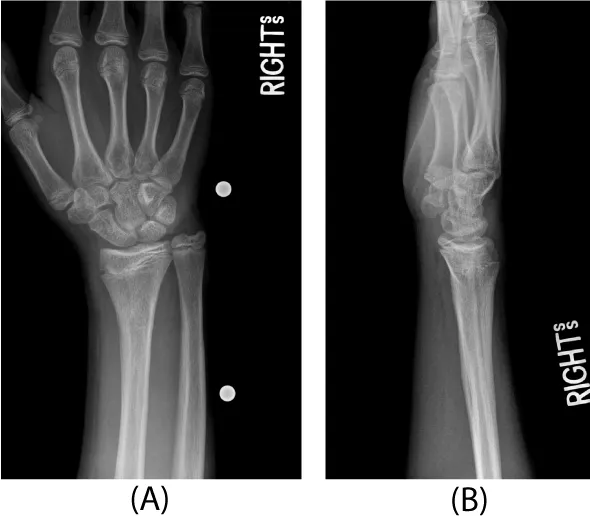

An 11 year-old right-hand-dominant healthy male presented after sustaining an isolated injury to his right wrist while snowboarding two days prior. The patient was seen at an outside emergency room and a splint was applied without manipulation. On examination, he had a normal neurovascular exam and full digital motion. An obvious clinical deformity was present. Radiographs of the right wrist revealed an extra-articular, extra-physeal distal radius fracture with dorsal angulation.

Three days after injury, consent was obtained, and the patient was taken to the operating room. There he underwent a manipulative closed reduction. Once reduction was obtained, percutaneous pin fixation was utilized to stabilize the fracture. Under flouroscopic guidance, two smooth 0.062 inch Kirschner wires were placed into the radial styloid tip and across the fracture site (Figure 2). Both pins were placed uneventfully with one attempted insertion. There were not multiple passes. The patient was then placed in a short arm cast that was split in the operating room.